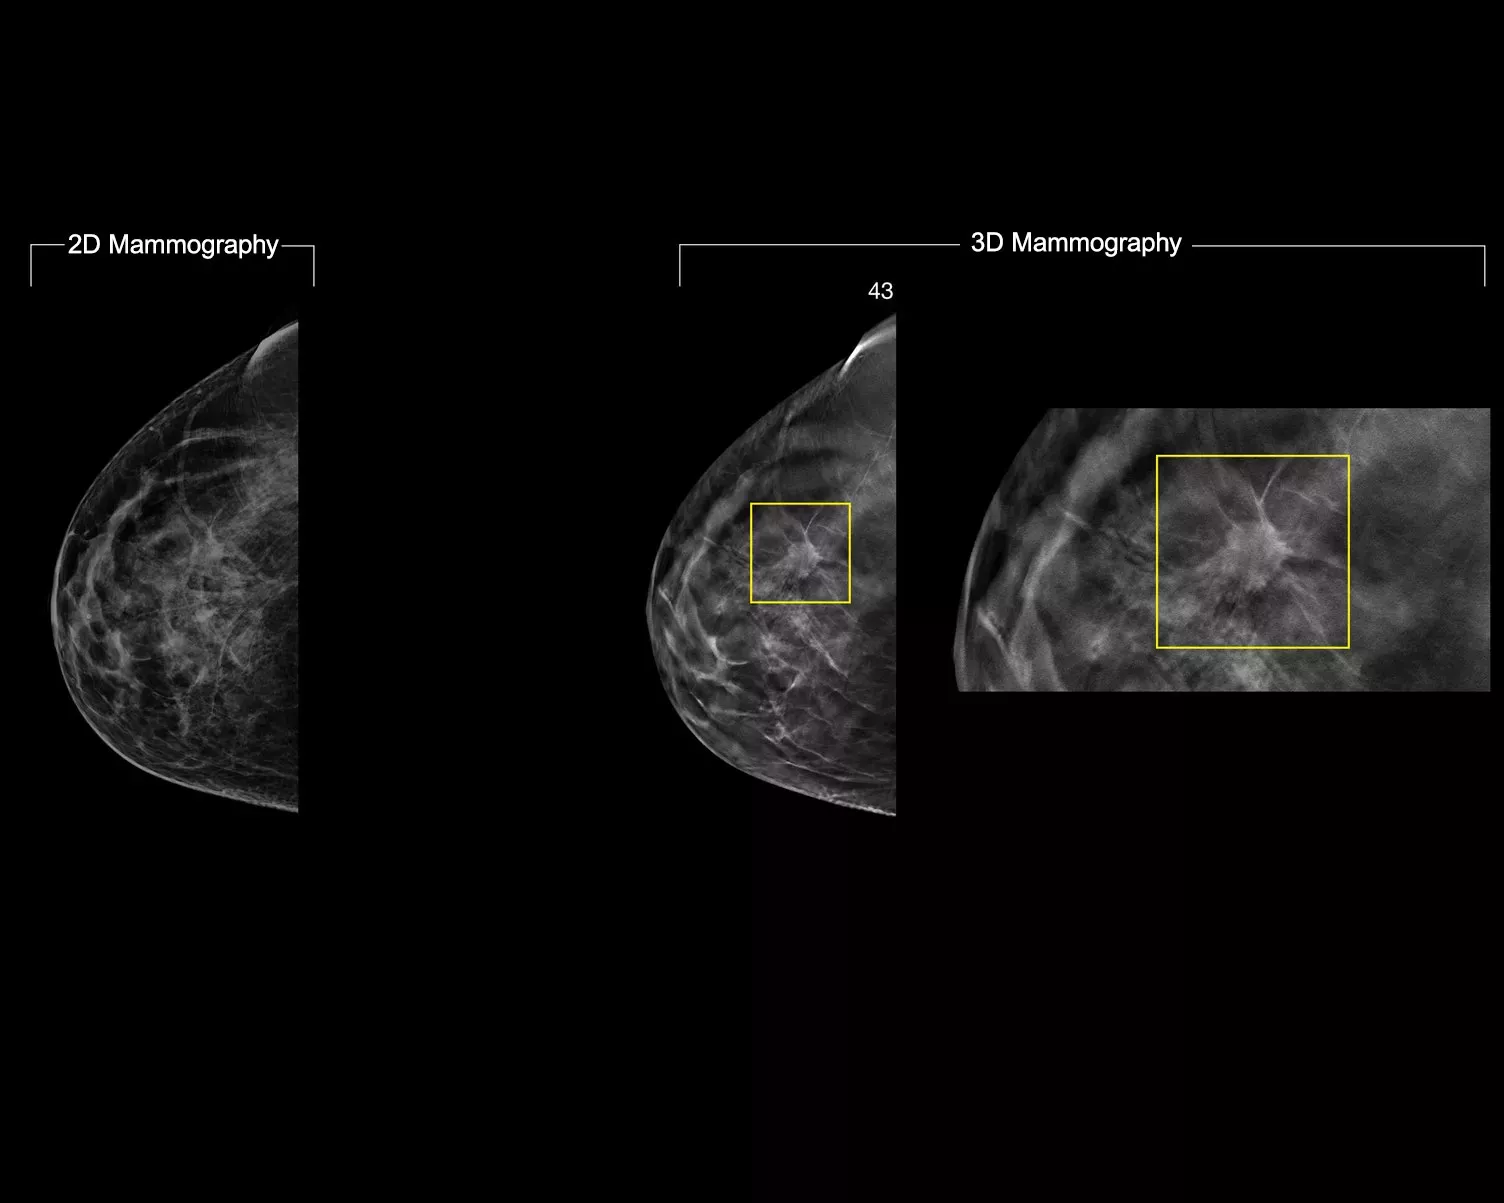

A deep-learning algorithm designed to aid radiologists' diagnostic performance of detecting breast cancer1-3 from tomosynthesis images obtained by using the Hologic Dimensions Mammography™ Systems. The algorithm locates lesions that are likely to represent breast cancer by searching each slice of the tomosynthesis image set. The suspicious areas are highlighted for concurrent reading at the radiologist's workstation to aid in interpretation.

The algorithm looks for 3 main groups of suspicious lesions: calcifications, masses, densities and distortions, and any combination of these lesions. Outputs may vary on different reading workstations.